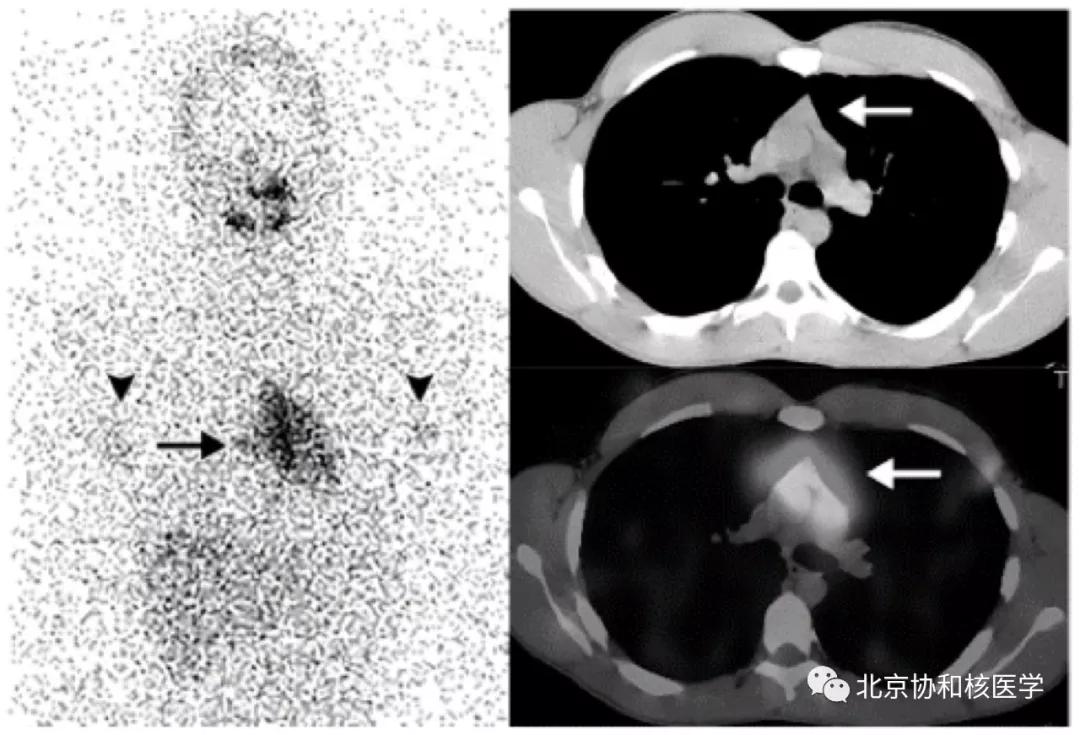

63岁女性,甲状腺癌病史,肺内不典型分支杆菌感染所致碘摄取:

肺内曲霉菌球摄取:

肺鳞癌所致碘摄取(后位图像),同时可见颈部甲状腺残余病灶: